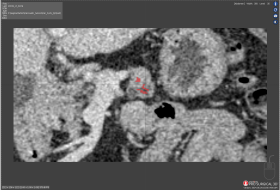

Scan 30: Bleed of 46,932

Bleed

Bleed is the area of the Test segmentation that covers area outside of the Ground truth segmentation.